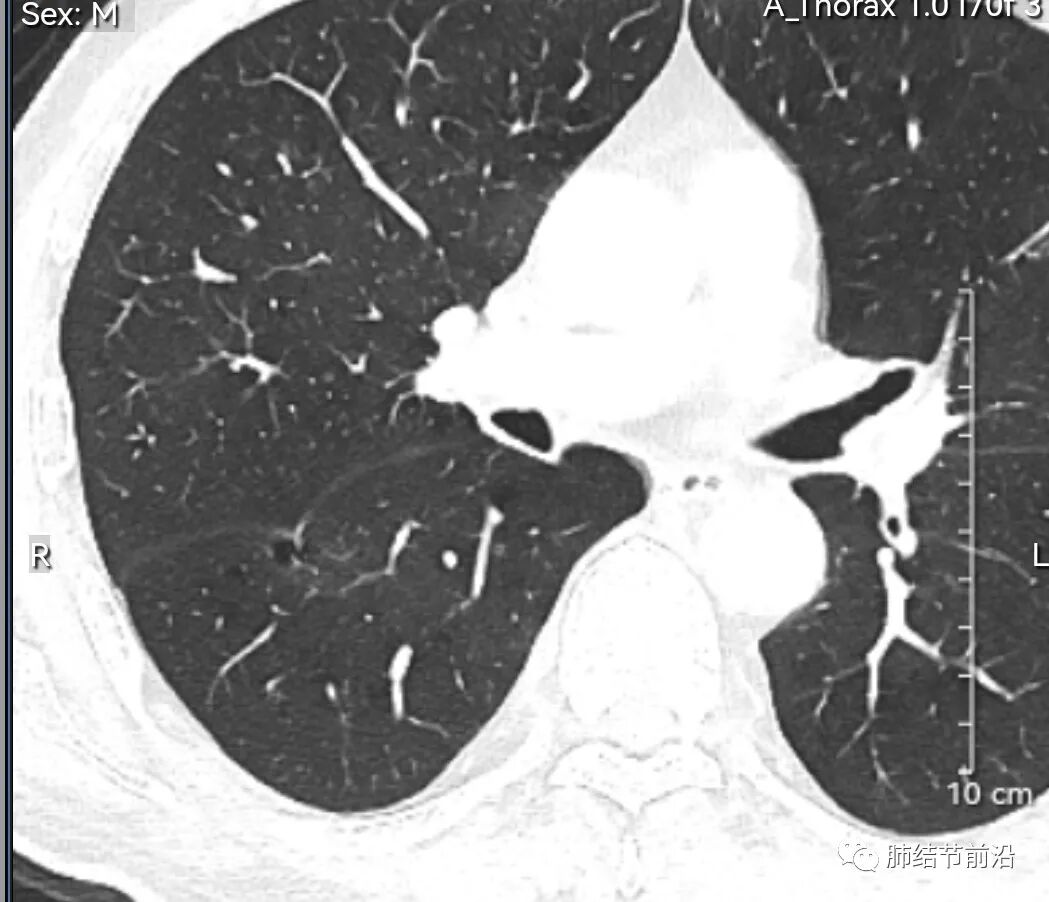

男性,67岁,重度吸烟史。CT发现右下肺囊腔。来看一下这个CT的特点:

该囊腔形态非常有特点,和常见的圆形肺大泡有很大的区别。

1.囊腔中央实性成分,周围有磨玻璃影。

2.囊腔中央有血管。

3.囊腔外周有分叶形态。

4.囊腔有胸膜牵拉。

出现这几种形态,CT可以确认恶性的腺癌。这个囊腔形成的机制,为肿瘤实性成分堵塞细支气管形成活瓣,肺泡内压力增高破裂行成,因此肺内血管成分保留。由于肺泡压力增高,而呈分叶状。另外,也有肿瘤的胸膜牵拉这一特点。

囊腔周围磨玻璃+囊腔中央血管为特征性表现。如果持续存在,几乎可以100%确认为早期肺腺癌。

建议患者手术切除,术后病理为浸润性腺癌,腺泡型,部分为实体型。IA1期,术后不用治疗。